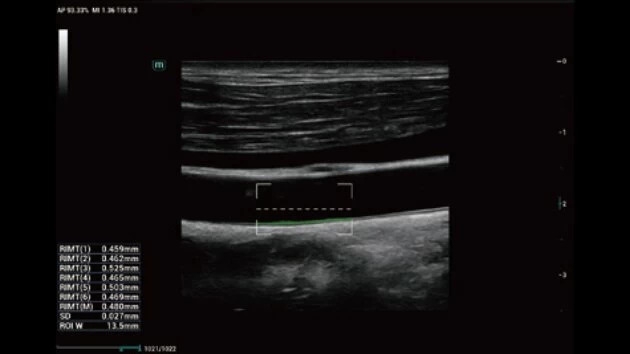

• Широкий спектр клинических исследований

• Расширенные возможности визуализации различных органов и тканей

• HD Scope технология для увеличения пространственного разрешения в зоне интереса